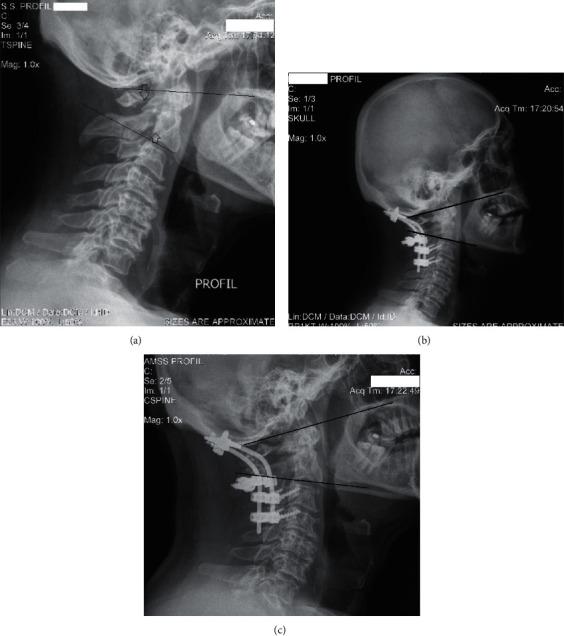

The primary outcome measure is the evaluation of sagittal cervical alignment roentgenographic parameters and the secondary is the functional outcome (NDI), following POCF for upper (C1 & C2) cervical trauma (UCT) in coexistence with upper cervical spine degeneration. . Twenty old and elderly patients aged 62 ± 12 years with evident upper cervical degeneration, who received POCF for upper C1 & C2 unstable cervical spine injuries, were included. C2-C7 lordosis, C2-C7 SVA, spinocranial angle (SCA), T1-slope, neck tilt (NT), thorax inlet angle (TIA), cervical tilt (CT), cranial tilt (CrT), and C0-C1 angle were measured. The subfusion angle was used to study the behavior of the unfused cervical segments below fusion. The Neck Disability Index (NDI) was used for the functional outcome evaluation. 29 age-matched individuals were used as controls for radiographic analysis and self-reported functional status comparison.

The roentgenographic data were measured 3 and 39 ± 12 months postoperatively. Twelve patients showed no disability, and eight showed mild disability. Postoperatively, the patients stood with less C2-C7 lordosis, SCA, and CT ( < 0.02) but with higher NT ( < 0.02) in comparison to the controls. The patient's neck disability (NDI) was increasing as TIA increases (=0.023). Subfusion angle seems to adapt to C2-C7 lordosis ( < 0.0033) and C0-C2 angle ( < 0.003) without any changes till the last evaluation.

主要观察指标是评估POCF治疗合并上颈椎退变的上颈椎(C1和C2)创伤(UCT)后颈椎矢状位对线的影像学参数,次要观察指标是功能结局(NDI)。纳入20例年龄在62±12岁、存在明显上颈椎退变、因C1和C2颈椎不稳损伤接受POCF治疗的老年患者。测量C2-C7前凸、C2-C7矢状面垂直轴(SVA)、脊柱-颅骨角(SCA)、T1斜率、颈部倾斜度(NT)、胸廓入口角(TIA)、颈椎倾斜度(CT)、颅骨倾斜度(CrT)和C0-C1角。用融合下角度研究融合下方未融合颈椎节段的情况。采用颈部功能障碍指数(NDI)评估功能结局。选取29例年龄匹配个体作为影像学分析和自我报告功能状态比较的对照。

术后3个月及39±12个月测量影像学数据。12例患者无功能障碍,8例有轻度功能障碍。术后与对照组相比,患者站立时C2-C7前凸、SCA和CT减小(P<0.02),但NT增大(P<0.02)。患者的颈部功能障碍(NDI)随TIA增加而增加(P=⁠0.023)。融合下角度似乎适应C2-C7前凸(P<0.0033)和C0-C2角(P<0.003),直至最后一次评估均无变化。